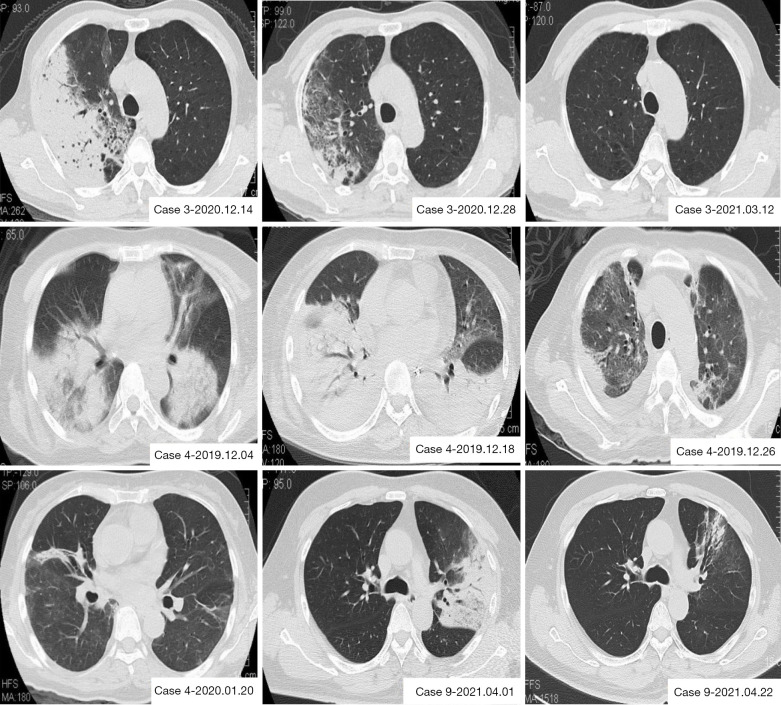

L’imaging radiologico è essenziale. La radiografia del torace mostra tipicamente infiltrati a focolaio o interstiziali, spesso monolaterali all’inizio, con una predilezione per i lobi inferiori.

La TC del torace è più sensibile e può evidenziare aree di consolidamento parenchimale circondate da un alone di vetro smerigliato (halo sign) o piccoli noduli centrolobulari.19